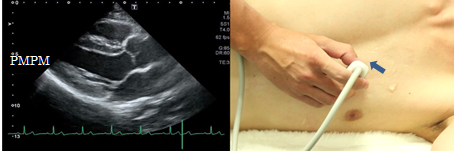

From the anterior commissure to the posterior commissure

The anterior commissure is visualized when tilted the probe slightly outward from the mitral valve mid portion so that the ultrasound beam is directed to outer side. At this time, adjust the probe so that the anterior papillary muscles, chordae tendineae, and the mitral valve are visualized in succession. The posterior commissure is visualized when tilted the probe slightly inner ward from the mitral valve mid portion so that the ultrasound beam is directed to inner side. These views are suitable to observe the site of a prolapsed mitral valve or a lesion of mitral valve stenosis and subvalvular apparatus.